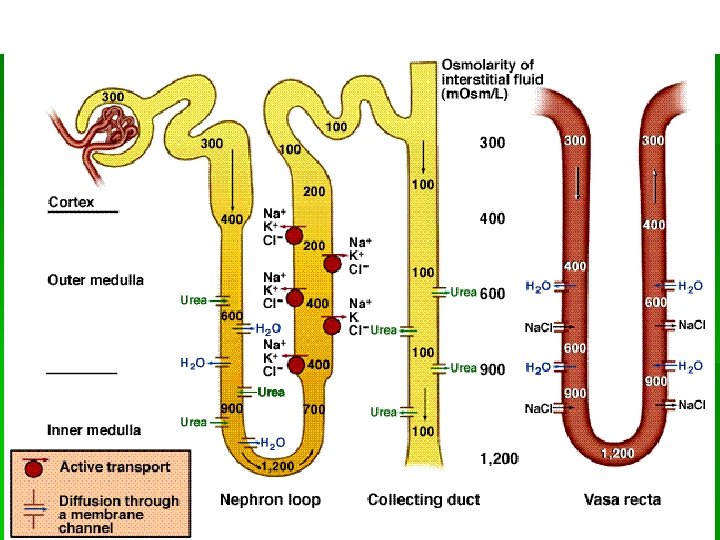

Нефрон – структурная единица почки § § Клубочковая фильтрация Канальцевая реабсорбция Канальцевая секреция Синтез новых соединений